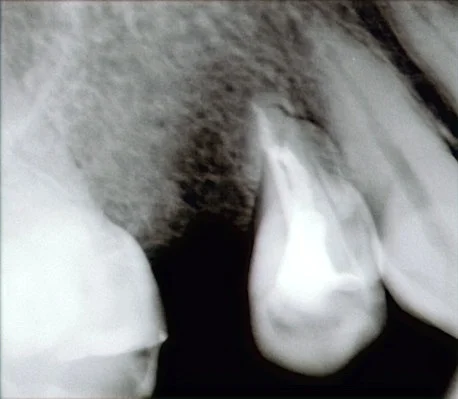

そしてこの歯は神経の治療をした歯だったので、根の先に膿が再発していないかを知る必要がありました。

そのため部分的な小さなレントゲンで撮影して診査したのがこちらです。

(ちょっと画像が暗かったのでこのHPの画像編集で編集して明るくしてみましたが、割といいですね・・・(●´ω`●))

4年前にあった根の先の膿があった黒い部分が完全に消失し、神経の治療がうまく行っているのが分かりましたので、今回は神経の治療には入らないことにしました。